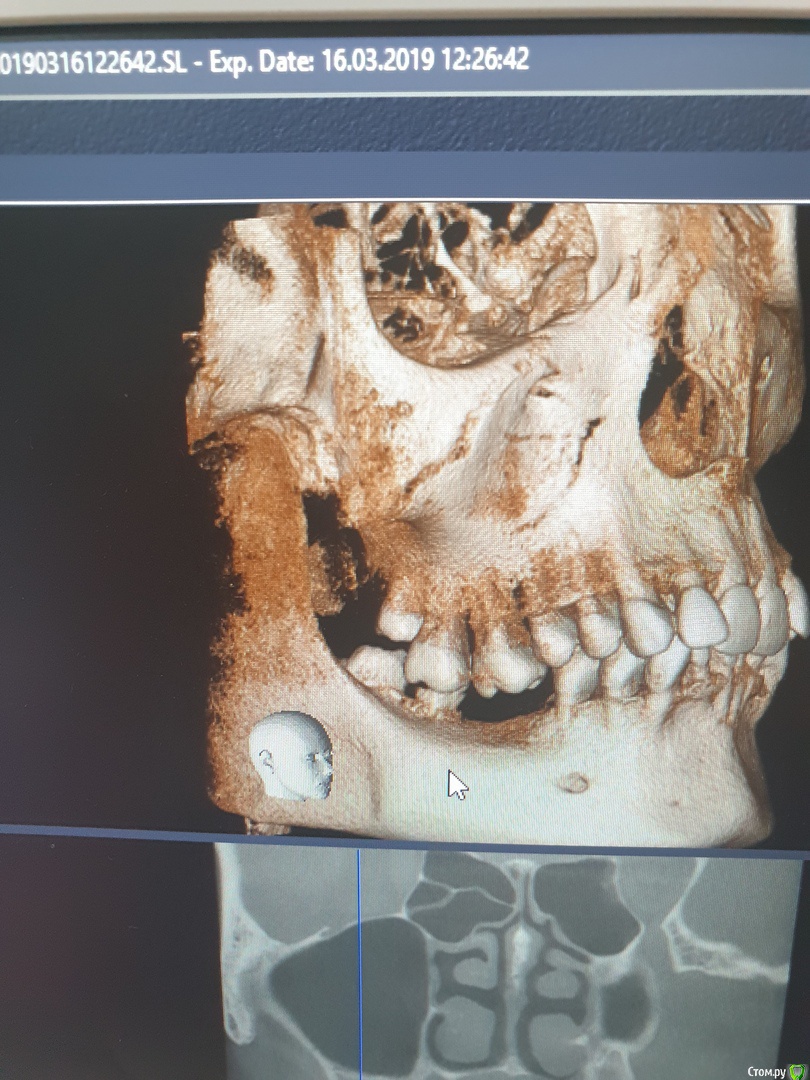

ArtDenis Опубликовано 29 июля, 2019 Поделиться Опубликовано 29 июля, 2019 (изменено) Добрый день. Заранее спасибо за Ваши ответы. Пациентка: Девушка, 30 лет, готовимся к первой беременности, поэтому занялись зубами. Снизу в челюсти долгое время отсутствовали зубы, по этой причине верхние зубы опустились вниз.Нижний 7-ой корень и 8-ку мы уже удалили. Ходили к нескольким ортодонтам и у них расходятся мнения по подъему опустившихся зубов.1) Чтобы поднять зубы, нужно удалить верхнюю возьмерку, а затем с помощью мини-импланта (какие-то небольшие шурупы) поднимать зубы.2) Восьмерку сверху удалять не нужно, так как за нее можно будет зацепиться и с помощью упора поднимать зубы мудрости. Эта восьмерка, кстати, вообще не открыта. Какой из вариантов более правильный, как Вы считаете?СпасибоPS: Так как все это затягивается, мы скорее всего сначала все-таки забеременеем, а потом уже будем спокойно заниматься зубами. Могут ли еще сильнее опуститься нижние зубы?Так как верхние восьмерки полностью закрыты и не беспокоят, какова вероятность того, что с ними будут проблемы во время беременности? Изменено 29 июля, 2019 пользователем ArtDenis Ссылка на комментарий